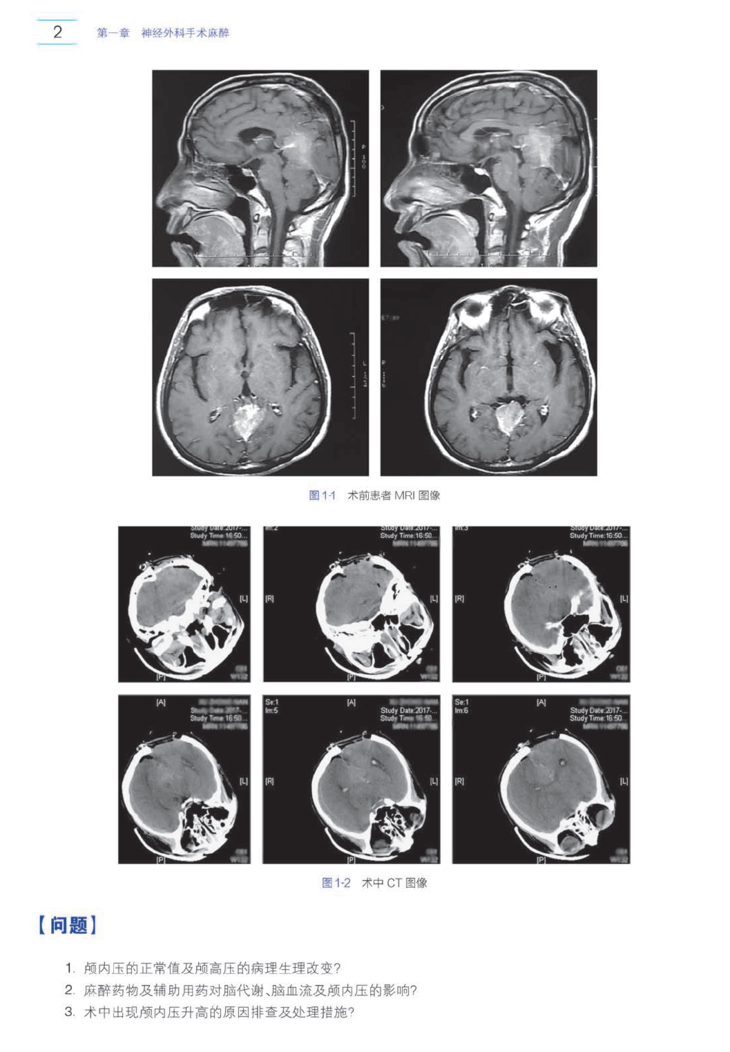

本书在涵盖临床麻醉的各个领域的前提下,精选出140多个来自临床的真实病例,包括了从临床常见病的麻醉管理到麻醉危重疑难病例和各种紧急事件。所有病例分析均出自全国几十名临床一线的知名中青年专家的亲身实践并亲自执笔编写。每一份病例均经过查阅大量文献和书籍,并以问题为导向,对病例进行简洁清晰的分析,抽丝剥茧,逐步深入,为读者提供全面的解答及实用的临床处理要点,总结经验和教训。同时,附上参考文献,方便读者进行延伸阅读。